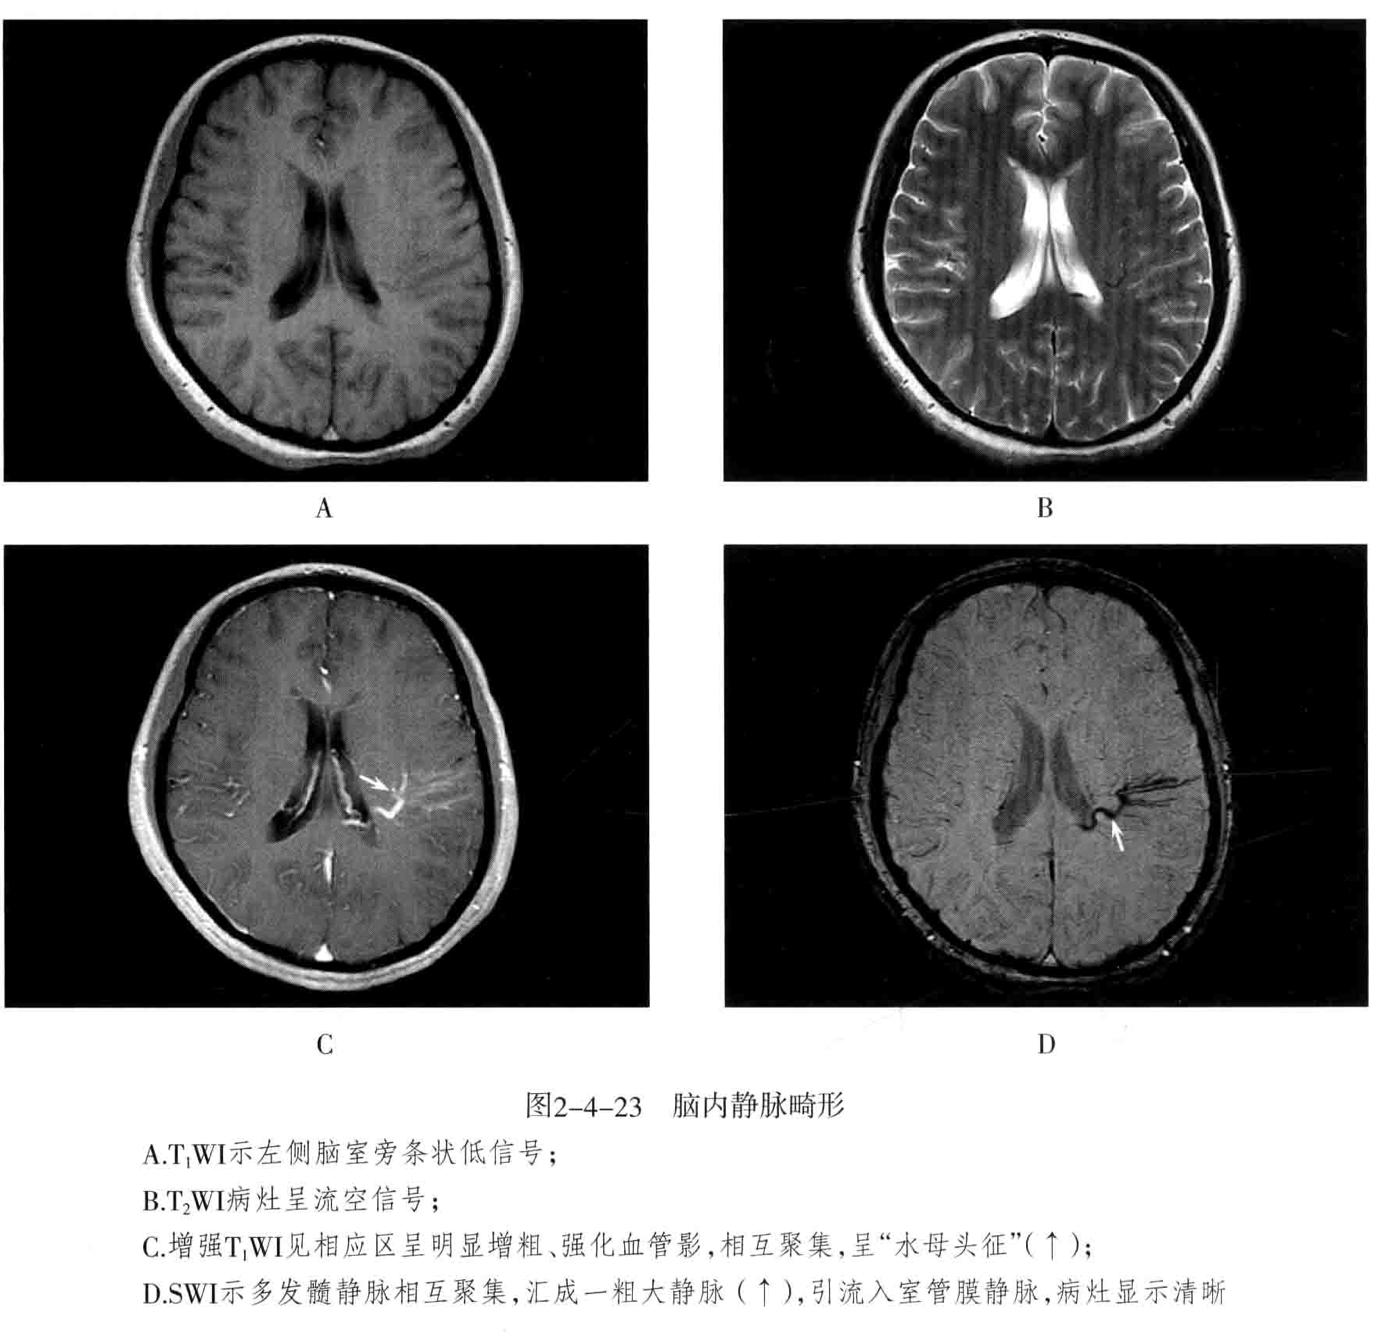

- 脑静脉性血管瘤 极为少见。静脉性血管瘤是一种组织上完全由静脉成分构成的脑血管畸形,任何年龄均可见,病理特点为许多放射状排列的扩张髓静脉连接成一条或多条扩张的经皮质或室管膜下引流静脉,最后汇入静脉窦。常发生于 额叶及小脑,以第四脑室周围多见 ,常伴发其他血管畸形,最常见为海绵状血管瘤。

- CT表现:平扫显示不清,周围无脑水肿,有时可见出血等改变,CTA典型表现为额叶或小脑许多细小髓静脉放射状汇入一条或几条引流静脉,最后汇入静脉窦,呈“水母头征”。

- MRI表现:可因病灶大小及血流速度不同而在MRI上呈多种信号,T1WI、T2WI多呈流空信号,少数由于血流缓慢也可呈略高信号,FLAIR呈低信号。增强后髓静脉及引流静脉明显强化,典型者呈“水母头征”,引流静脉可走向脑表面而引流至静脉窦,或走向脑室引流至室管膜静脉。MRV可显示引流静脉及其引流情况,但不显示髓静脉,SWI序列对本病显示很敏感。病灶周围无脑水肿表现,有时可见出血。

- 鉴别诊断:动静脉畸形:由供血动脉、畸形血管团、粗大引流静脉构成。海绵状血管瘤:多可见不同时期反复出血的产物,周围脑实质多有脑萎缩改变,MRI呈爆米花样改变为特征,周边见含铁血黄素环,增强后轻度或无去强化。